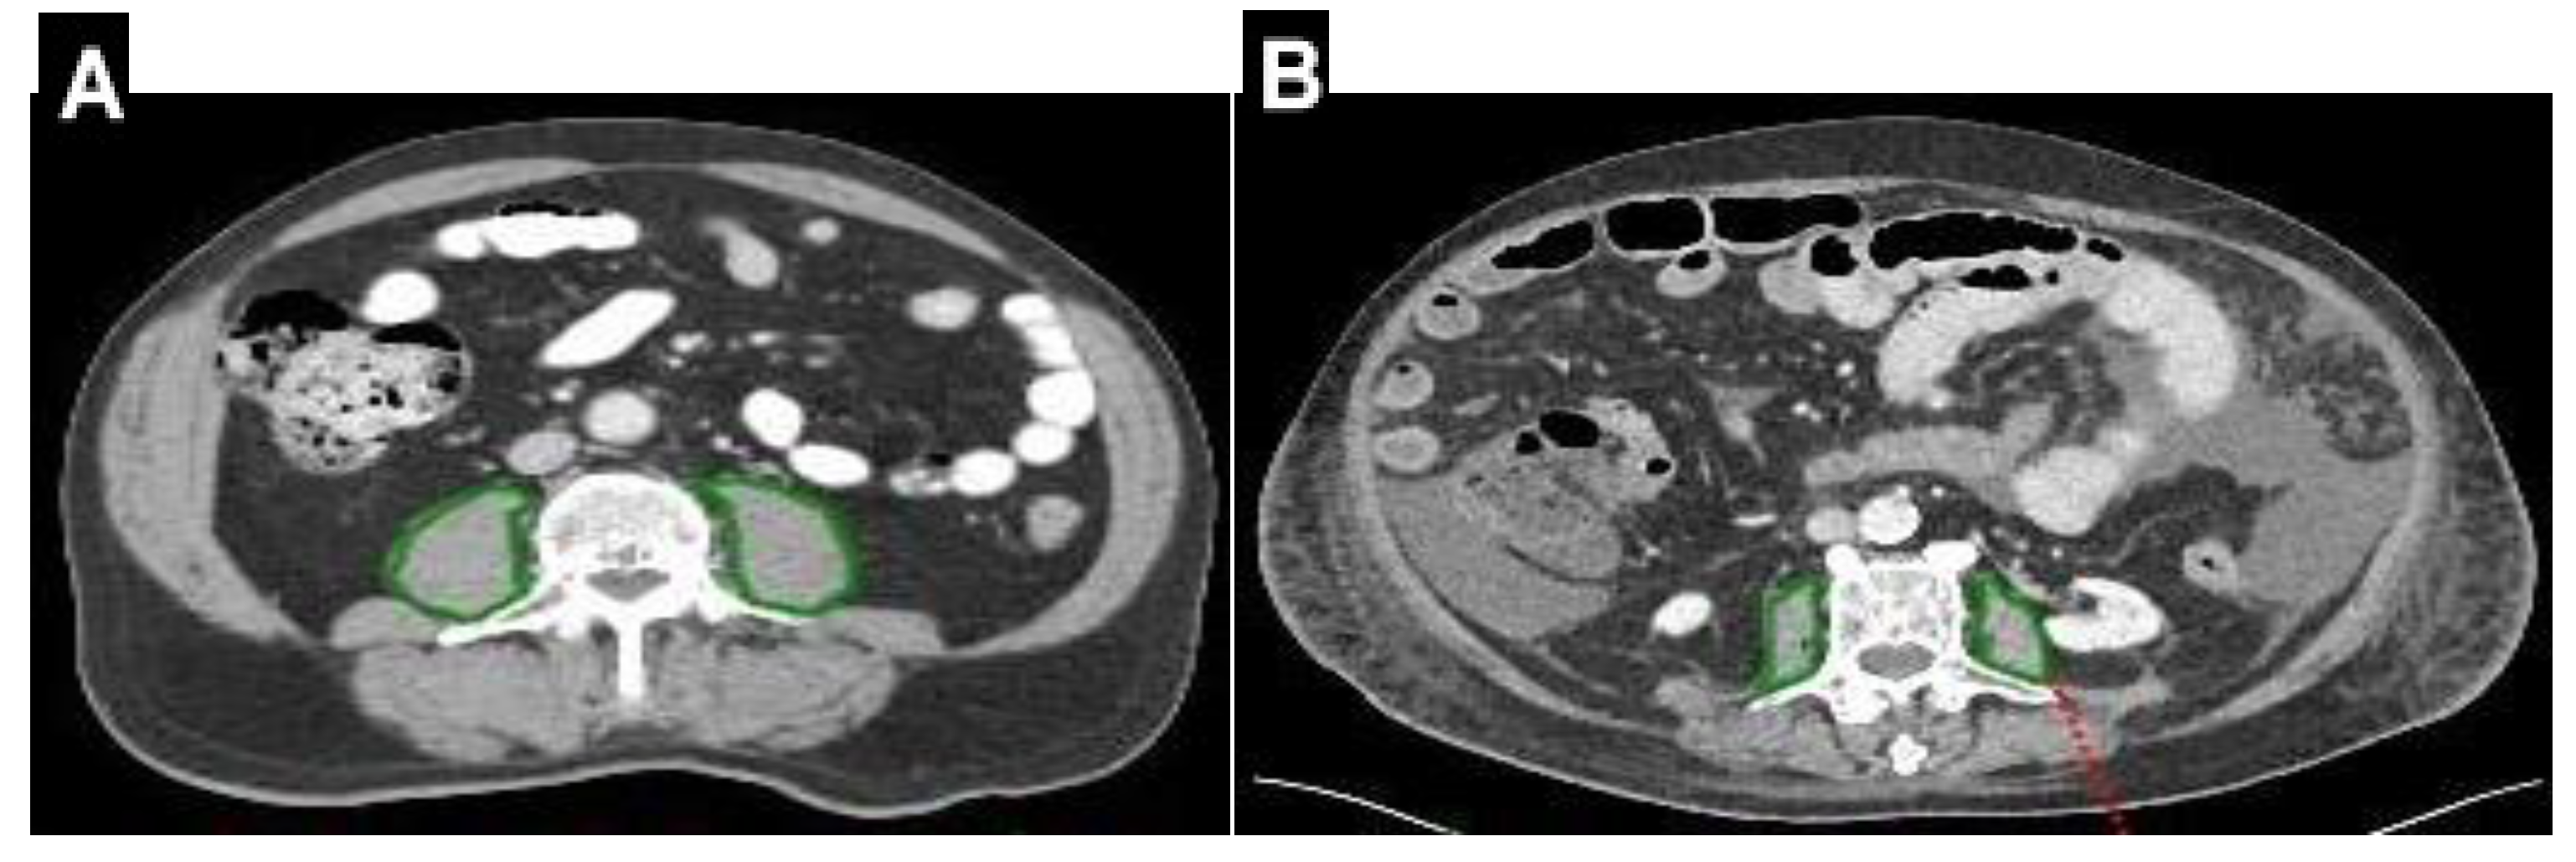

| Data of CT, mean ± SD: | |

| PMA, cm2 | 15.6 ± 6.3 |

| PMD, HU | 42 ± 8 |

| PMI, cm2/m2 | 5.42 ± 1.88 |